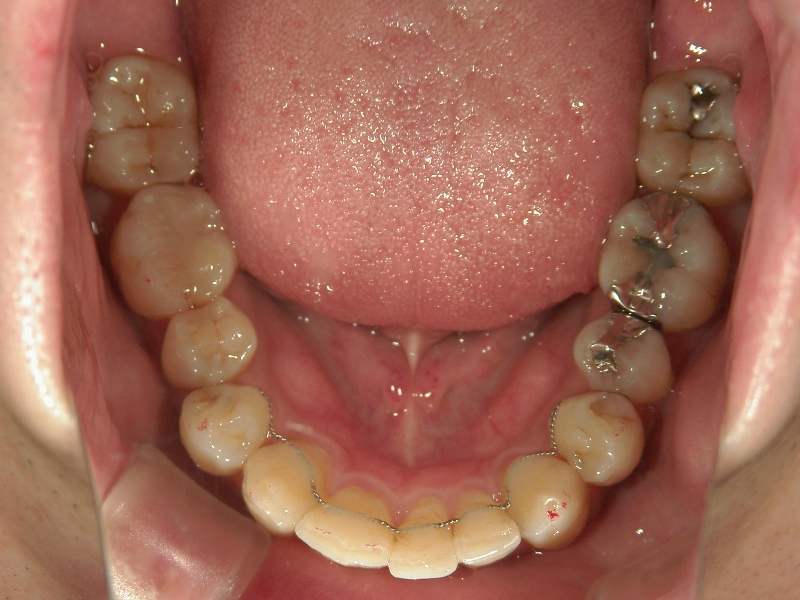

矯正歯科 治療前矯正歯科 治療前

33歳男性 浜松市東区在住

治療期間1年7ヶ月

主訴:前歯の歯並びが気になる。

矯正歯科 治療前 上顎の左右4番計2本を抜歯し叢生を改善。